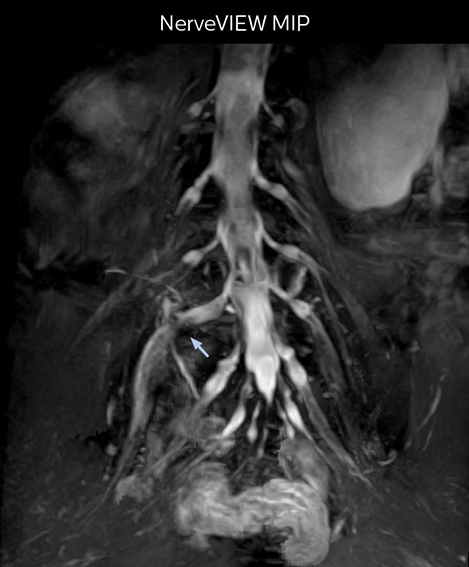

“In such case, we would then browse through axial T2-weighted MR images slice by slice and mentally reconstruct the actual situation based on both radiculography and MRI. Fortunately, NerveVIEW can now very well show nerve courses and presence of nerve compression or edema in one single image series.” “We have often seen NerveVIEW directly depict details of the nerve compression that were not observed by radiculography. Therefore, we think that with NerveVIEW we can reduce the number of invasive examinations, especially for some patients with lumbar plexus symptoms.”

The key concept in MR neurography, Dr. Yabuki stresses, is the ability to directly visualize spinal nerves, versus inferring the presence of pathology indirectly. “Before NerveVIEW, we estimated compression of the nerve by looking for the presence or absence of fat signal on other MR images,” he says.

“For example, in sagittal images, when the presence of fat is observed in the intervertebral foramen, it suggests that there is a margin around the nerve. Similarly, the absence of fat indicates that the nerve is being compressed. So, we used to deduce nerve compression indirectly. With NerveVIEW, however, we can observe the condition of the nerves directly, regardless of the presence or absence of fat. We always prefer such direct observation of anatomy over having to make an inference about it.”

“The intra-luminal signal of veins, especially around the intervertebral space, can be suppressed well with NerveVIEW. As a result, we can easily observe the detailed nerve structure around the posterior ganglion,” he says. “This is why we use 3D NerveVIEW for intraforaminal stenosis and extraforaminal stenosis/herniation (lateral disc herniation). On the other hand, if herniation is suspected to exist inside the dorsal root ganglion (DRG), balanced TFE or ProSet-FFE is applied. NerveVIEW is not suitable for evaluating the median type of herniation.” The SE-EPI DWI-based method for MR neurography works well for large FOV exams like whole-body MRI, but focal examination of nerves is often limited by the attainable spatial resolution (both inplane and slice direction) and geometric distortion. “3D NerveVIEW achieves higher in-plane resolution – close to our other routine spine sequences – and the source images can be used instead of adding a fat-suppressed T2-weighted sequence,” Tanji says.

According to Tanji, methods such as ProSet FFE, STIR or 3D VISTA are anatomically nonselective because background signals, for instance from blood vessels, often interfere with nerves, which hampers evaluation of details, especially at the peripheral side of the nerves.